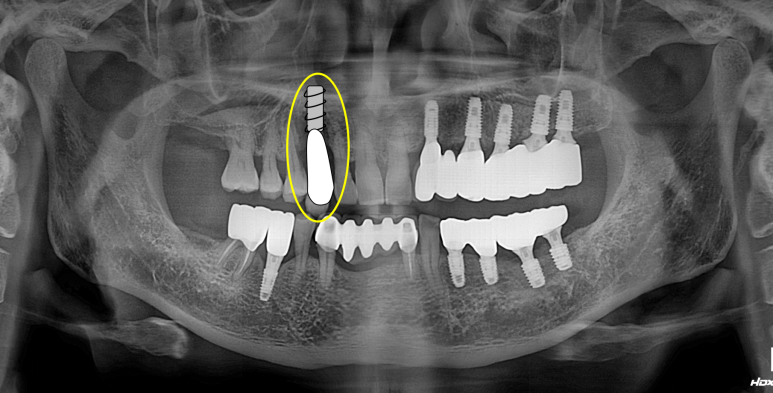

치과용 파노라마 엑스레이입니다.

임플란트가 무려 9개나 되어있네요! 여기에서 앞니 임플란트의 명백한 단점을 확인할 수 있습니다.

보이시나요? 바로 임플란트 크라운이 너~무 길다는 것.

잇몸질환 (만성 치주염)이 심하신 분들의 경우 잇몸뼈의 상실이 심해 결국 임플란트를 '깊게' 심게 됩니다.

결과적으로 치아 길이가 너~무 길어보여 결국 음식도 많이 끼고 비심미적인 (보기 안 좋은) 결과를 낳는다는 것...

사실 어쩔 수 없이 임플란트를 해야만 하는 상황이긴 하나, 잇몸뼈 염증이 심했을 땐 저렇게 어색한 임플란트 머리를 피할 수가 없습니다...

보이시는 것처럼 엄청나게 깊이 임플란트를 심어내고 결국 머리가 엄청 길어져버린 임플란트를 만들어드리게 된단 말이죠...

앞니 지르코니아 브릿지 접착 후 치과용 파노라마 사진입니다.

잘 보시면, 송곳니가 있었던 자리가 엑스레이 상에서 꽤나 어둡게 보이는 것을 확인하실 수 있으실텐데요,

실제로 CT를 찍어보면 아마 남아있는 잇몸뼈가 너무 적어 임플란트 수술에 상당히 곤란할 모양일 것입니다.

치료의 방향을 결정함에 있어서 경험을 통해 과정과 결과를 예상하고 보다 유리한 치료방법을 선택한 예임을 확인할 수 있었습니다.